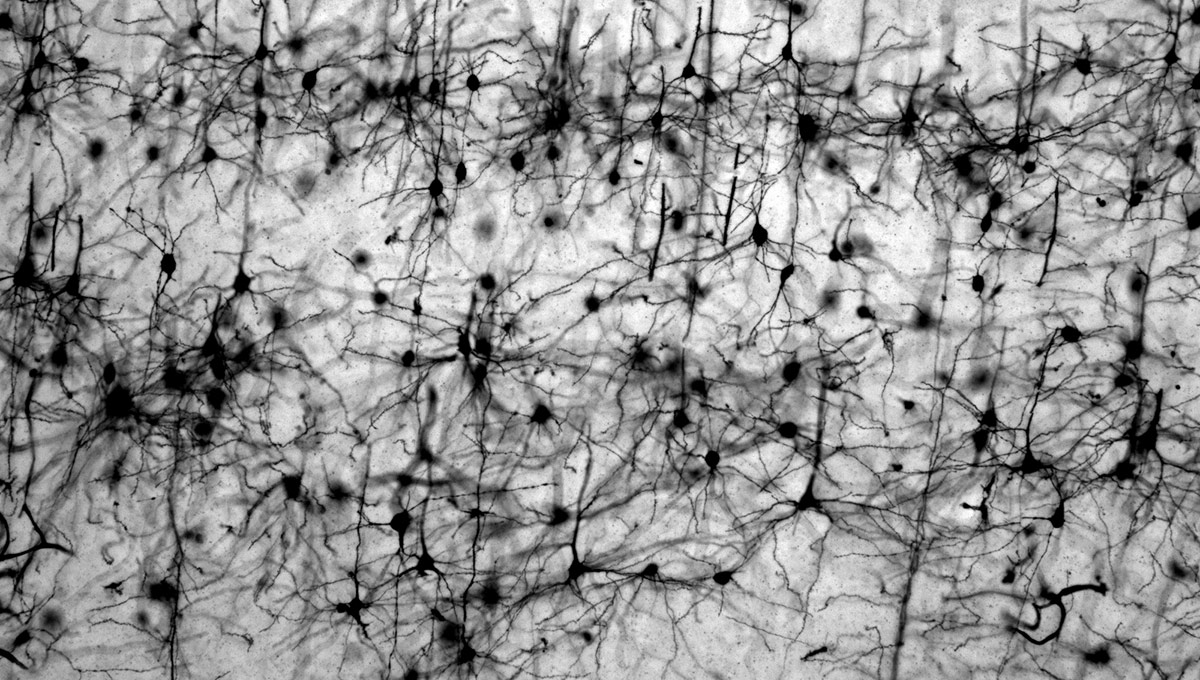

The green microscope image featured above is from Matthew Holahan’s experiments and shows the accumulation of a protein called alpha-synuclein in a mouse brain; the bright spots show alpha-synuclein aggregating into clumps of spaghetti-like filaments that, researchers believe, lead to decreases in dopamine and Parkinson’s symptoms such as slow movements, tremors and rigidity. The red image shows A-syn-1, the aptamer Holahan and Maria DeRosa designed to target the protein. The yellow image shows the successful co-localization of A-syn-1 and alpha-synuclein, which has the potential to help stop Parkinson’s disease. The black-and-white images, in order of appearance from top to bottom, show: dopaminergic neurons in the substania nigra, part of the midbrain where Parkinson’s pathology occurs and affects motor function — dopaminergic neurons are the main source of dopamine in the brain; the motor cortex, where Holahan and DeRosa’s research is focused; and what neurodegeneration looks under a microscope.